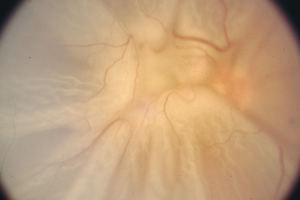

Proliferative Retinopathie – Augenärztliche Gemeinschaftspraxis | Dr. Heuring, Dr. Jung & Kollegen

Gefäßwucherungen und Einblutungen in den Glaskörper

Netzhautablösung mit Membranschrumpfungen